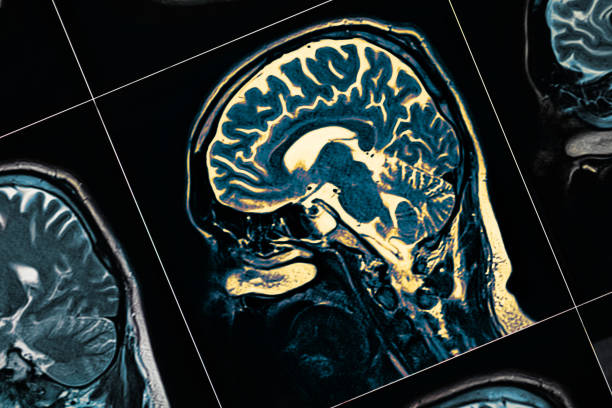

Diagnosis

To this date, there is no specific diagnosis of Parkinson’s, however, doctors make diagnoses based on health, physical and neurological disorders.

They will also review the signs and symptoms you are presently showing of this disease. Your doctor can use image testing to rule out other conditions.

Moreover, a DAT (Dopamine Transporter) scan can be used.

Most of the time it cannot diagnose Parkinson’s but it helps to rule out other conditions.